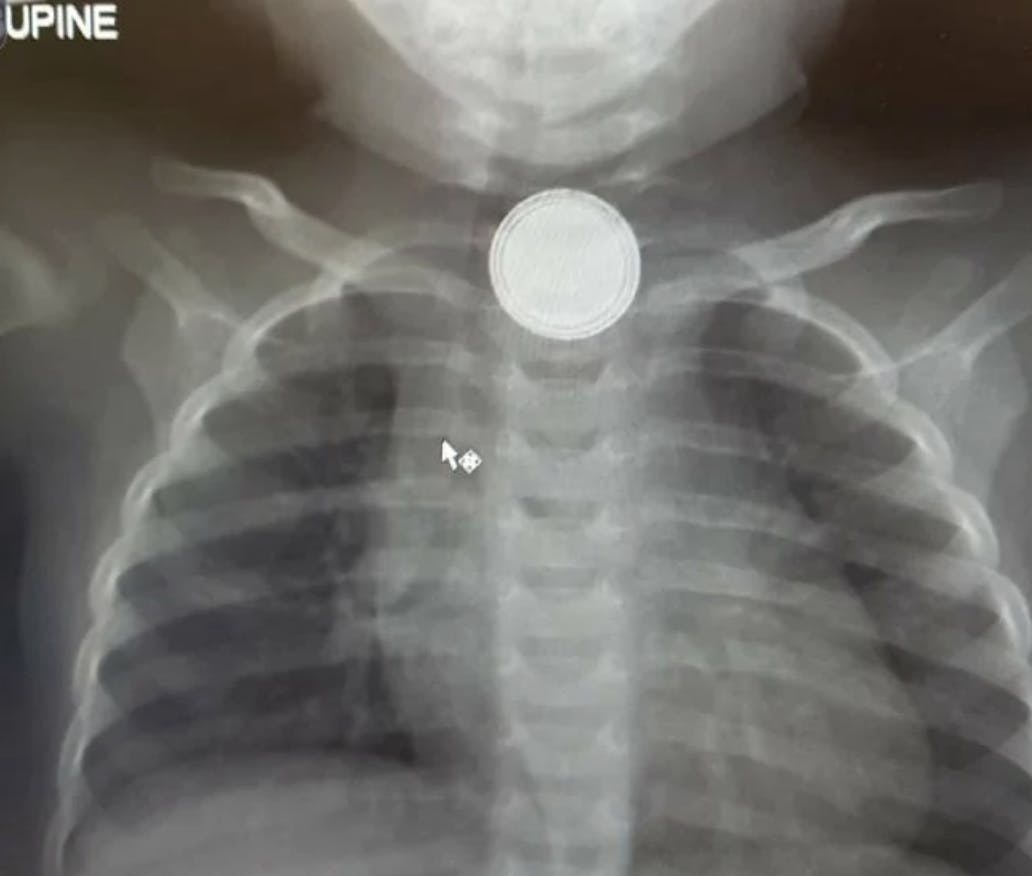

Emily hastede derfor sin lille datter til The Children’s Hospital i Westmead, Sydney, hvor en scanning straks afslørede, hvorfor hendes lille pige var så syg:

En 20 millimeter stort batteri sad fastlåst i lille Milas hals.

Artiklen fortsætter under billedet...

Batteriet var ikke til at overse. Foto: Supplied